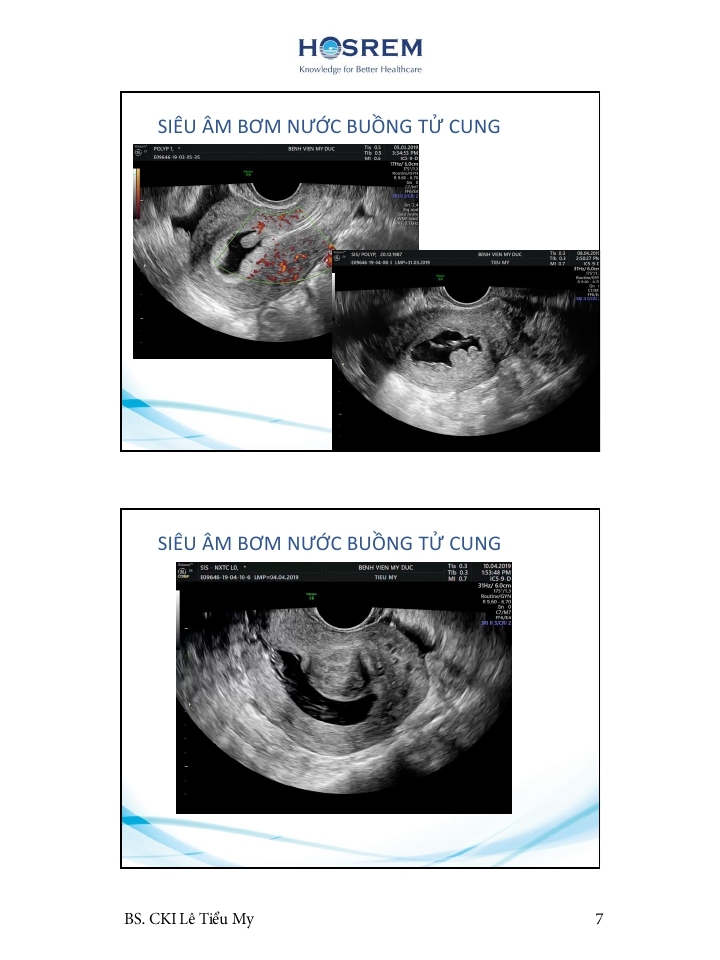

Các phương pháp đánh giá ống dẫn trứng